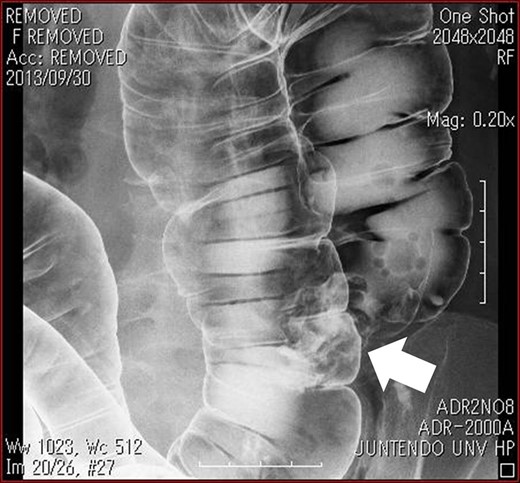

Abdominal CT scan showed complete inversion of the internal organs. 3D-CT angiography revealed no right colic artery and ileocolic artery was located ventral to superior mesenteric vein, and there was angioplany with the exception of mirror image (Fig. 2). Barium enema revealed an elevated lesion in the ascending colon (Fig. 3). Colonoscopy revealed an ulcerative tumor in the adjacent ileocecal valve of the ascending colon; biopsy confirmed that it was a well-differentiated adenocarcinoma. A laparoscopic right colectomy with radical lymphadectomy was performed by ambidextrous surgeon. Under general anesthesia with the patient in a modified lithotomy position, the operator and endoscopist were situated on the right, the first assistant was on the left, the reverse of the locations for orthotopic patients. Trocars also were placed in a mirror image manner, including a 12-mm umbilical trocar for camera, a 11-mm trocar in the right lower quadrant of the abdomen as working port for the operator, 5-mm trocars in the right upper, left upper and left lower quadrant of the abdomen (Fig. 4). The liver was located on the left and the spleen on the right. There was severe adhesion of sigmoid colon and mesentery of terminal ileum to the retroperitoneum. The duodenum had weak fixation to the retroperitoneum and malrotation (Fig. 5). The laparoscopic procedure was commenced breaking up the adhesion of sigmoid colon and mesentery of terminal ileum and retroperitonium. It took almost 40 minutes to break up. We then incised the peritoneal reflection of the terminal ileum to make a tunnel between the mesocolon and retroperitneum until the second portion of the duodenum and head of the pancreas were seen. The ileocolic vessels were identified and divided after the superior mesenteric vein exposed. Dissection of the lymph node started from ileocolic vessels and continued up of the root of surgical trunk (Fig. 6). Next, the remaining ascending colon was fully mobilized along Toldt’s fascia medially to laterally. By extending the 12-mm trocar of the umbilicus, on approximately 40-mm long vertical incision was made, through which we carried the ascending colon include the tumor out. Functional end-to-end anastomosis between the ileum and the transvers colon was extracorporeally performed using staple. No additional port was needed. Operation time was 237 min and the blood loss were 20 ml. Macroscopically, the tumor was a 40 × 40 mm ulcerated lesion in the adjacent ileocecal valve of the ascending colon. Histological examination of the resected specimen disclosed well-differentiated adenocarcinoma. Lymph node metastasis was found in 2 out of 11 nodes (StageIIIB: T3, N1, M0). The patient was discharged on the 12nd day after the operation, without any complication.

Barium enema revealed an elevated lesion in the ascending colon (arrow).